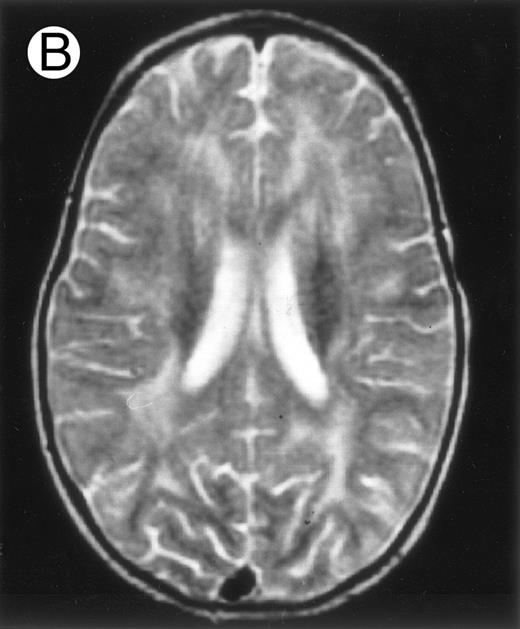

Among the nine children with initial neurological symptoms, seizures were the most frequent initial symptom in the youngest patients, whereas ataxia was found in the two oldest patients (46 and 58 months old, respectively) (Table 1). All nine patients had the same CSF abnormalities as patients with meningitis only. Eight of these nine patients had a neuroradiological study performed at the time of their first neurological symptoms (Table 1). The two most frequent lesions were focal necrosis with parenchymal volume loss and atrophy (Fig 2A and C) and white matter abnormalities (Fig 2B). Several small focal lesions with hypersignal at MR imaging that enhanced after administration of gadopentate dimeglumine (or contrast on CT scan) were also observed in two cases.

Three different aspects of brain imaging in HLH patients. (A) CT scan of a 3-month-old baby showing a large subdural effusion, several necrotic areas and hypodensities of the white matter. (B) Brain magnetic resonance of a 14-month-old boy showing large confluent areas of hypersignal in T2-weighted images. (C) Large symmetrical necrotic areas of cerebellar white matter in a 41/2-year-old girl (MRI).